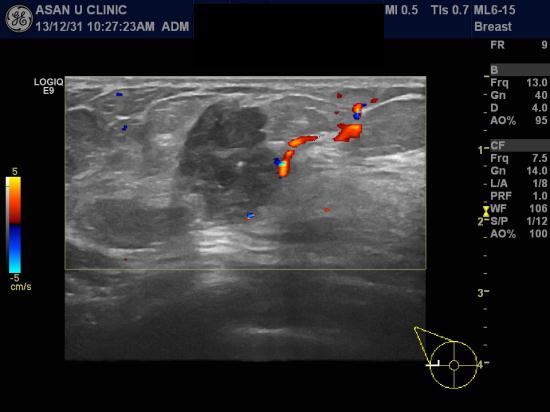

아산유외과 개원 후 52번째 유방암 진단.

우측 유방에 만져지는 몽우리가 갑자기 생겨

본원 유방초음파통해 우측 유방에 2.8cm, 0.9cm의 두개의 혹과

우측 겨드랑이 림프절의 비대소견이 발견된 43세 여성분입니다.

조직검사와 세포검사로 우측 유방의 침윤성 유방암 진단되었으며

안타깝게도 림프절 또한 암이 퍼진 상태였습니다.

향후, PET scan, 유방 MRI로 암이 어디까지 퍼진 상태인지 확인해봐야 하는

중요한 과정이 남아 있습니다.